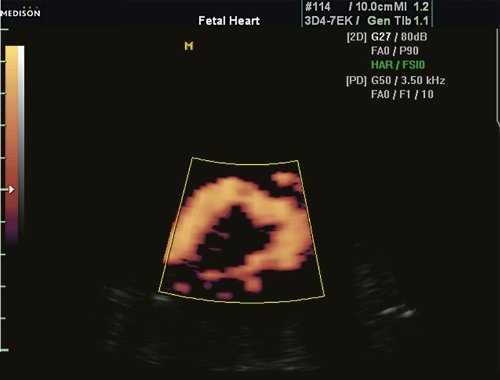

1. Эхокардиография.

Фетальная ЭхоКГ: внутриутробная диагностика перерыва дуги аорты (как и изолированной коарктации аорты) представляет значительные трудности. Косвенные признаки порока - асимметрия желудочков с преобладанием правых отделов и уменьшение скорости кровотока в восходящей аорте.

Рис. 1. Восходящий отдел, дуга и нисходящий отдел аорты плода в режиме энергетического допплера в норме.